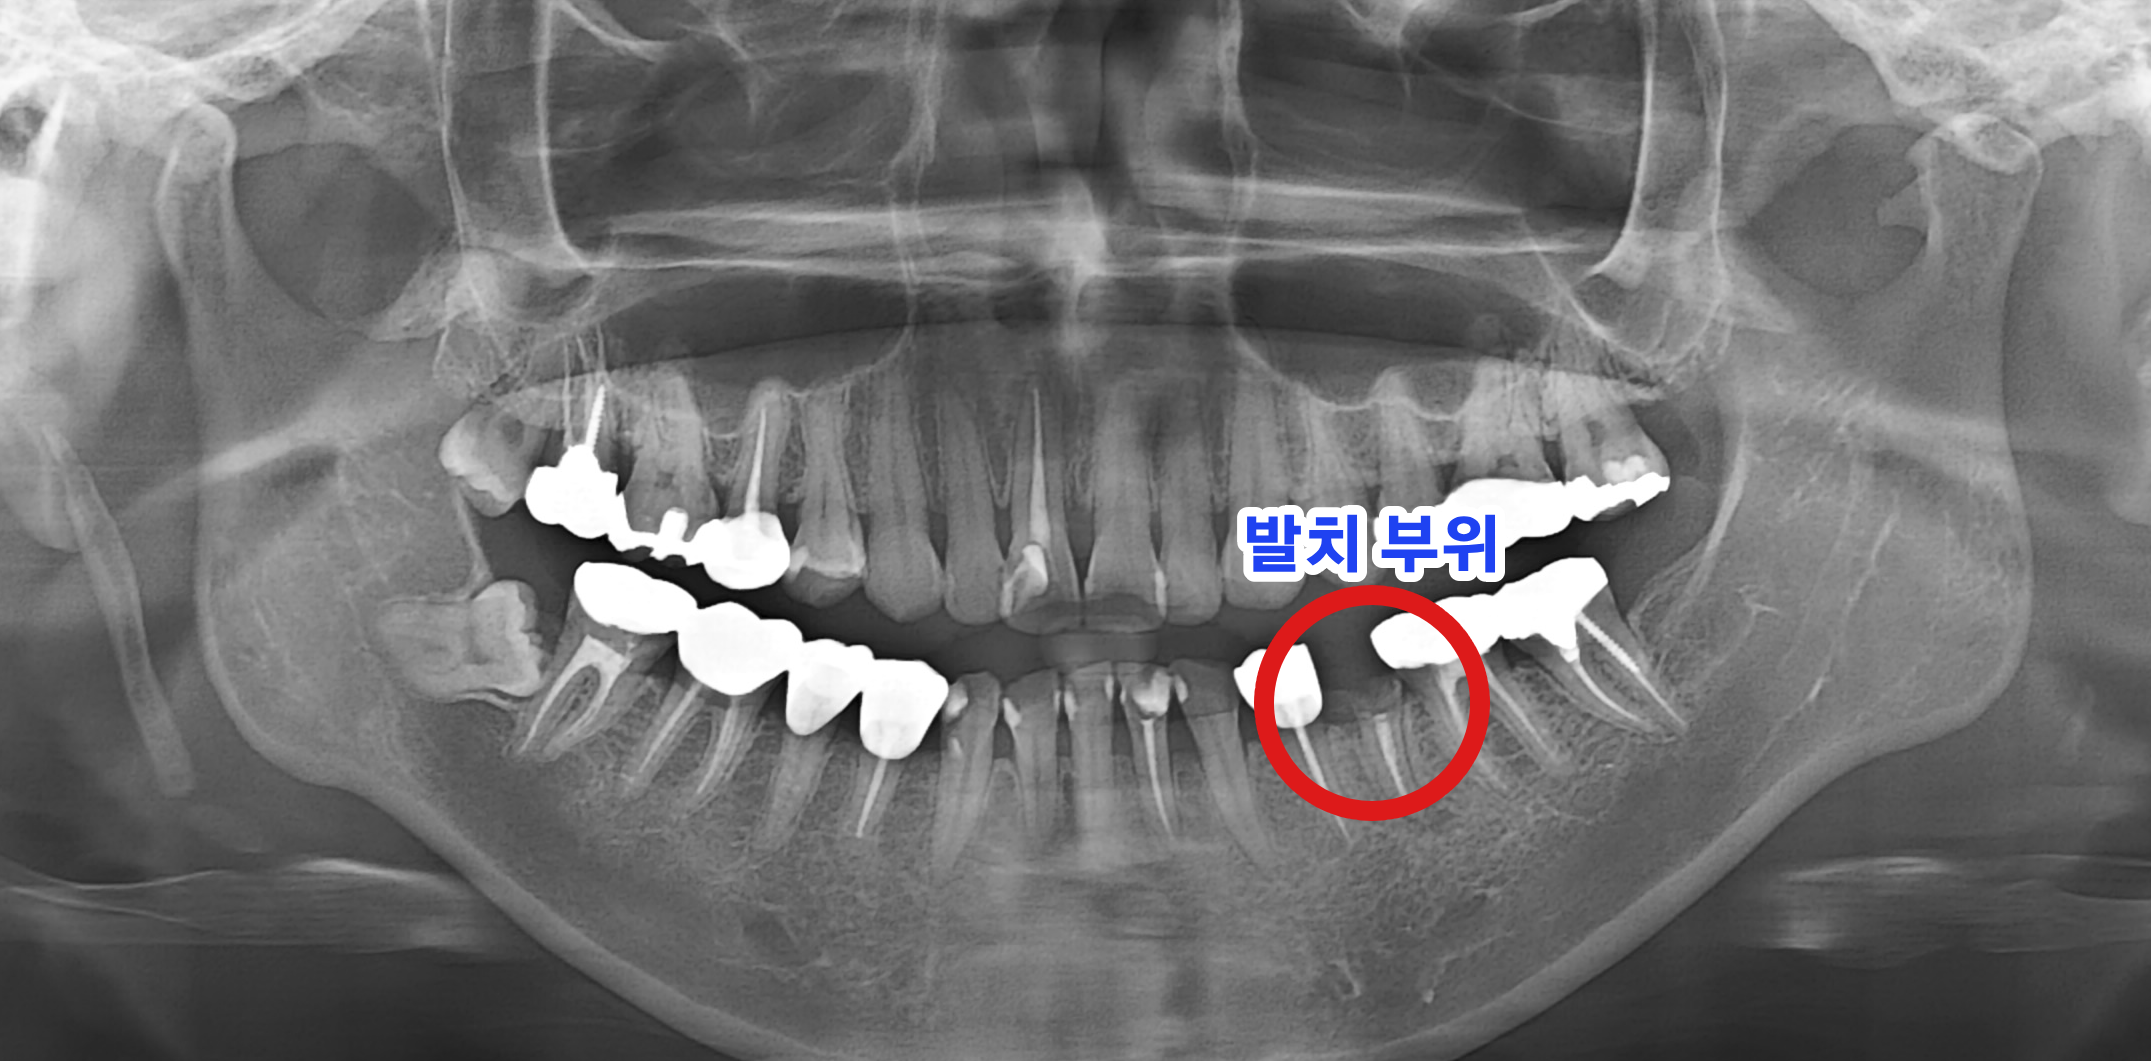

BEFORE 치료 전 발치된 치아 부위

치료 전 : 35번 치아 발치 후 상태 (촬영일 : 2025.08.12)

환자분은 왼쪽 아래 작은어금니(#35)가 치아 뿌리만 남은 상태로 내원하였습니다. 방사선 사진 및 구강 검사를 통해 임플란트 식립을 위한 잇몸뼈 상태를 정밀하게 진단하였습니다.